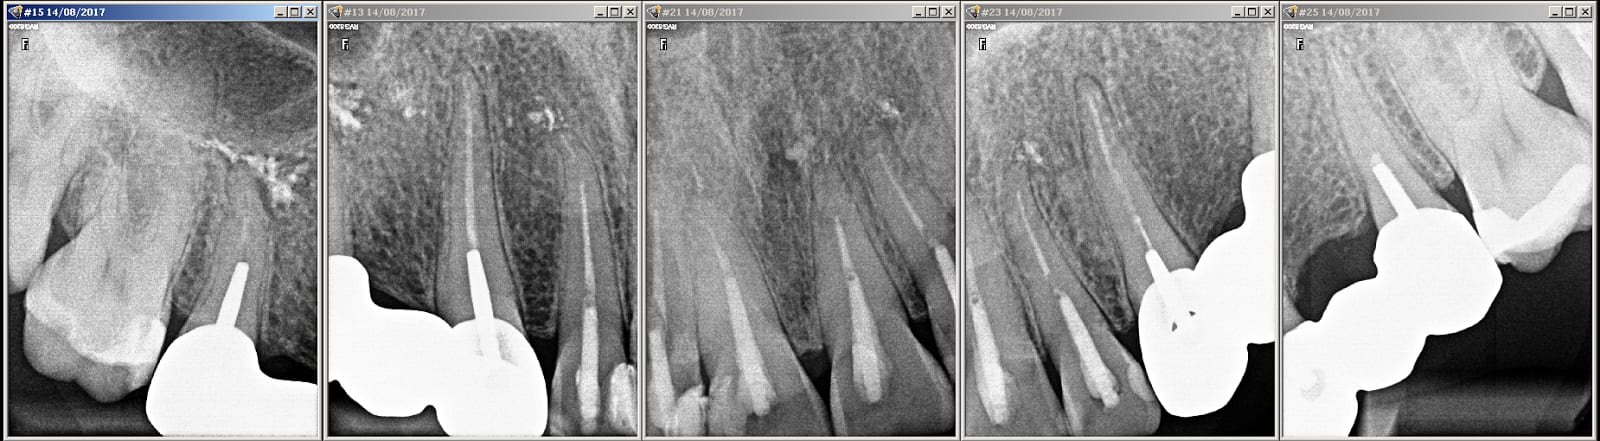

14/08/2017 à 16h57

Effectivement pas facturé les rte...

Bon et bien le haut maintenant...

Img 1606 y7zgvi - Eugenol

Img 1610 lptn89 - Eugenol

Img 1615 rpdoqy - Eugenol

Img 1653 obrh1p - Eugenol

Img 1613 ytxave - Eugenol